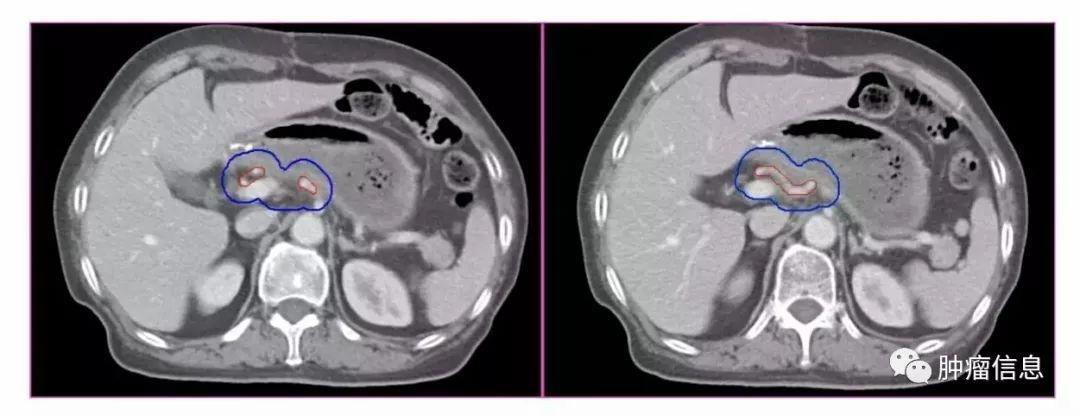

No.14肠系膜根部淋巴结

分为:肠系膜上动脉组(14a)和肠系膜上静脉组(14v)